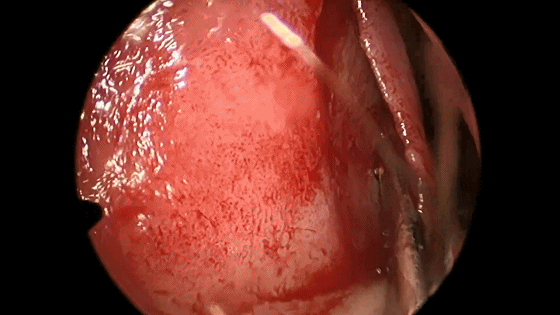

▼将左侧黏软骨膜从鼻中隔上分离,直到暴露后方的蝶骨嵴和蝶嘴。

▼使用磨钻在犁骨和筛骨垂直板后部 上下方向磨开鼻中隔骨质。

▼分离对侧黏软骨膜与鼻中隔间隙,直至完整暴露双侧蝶嘴至蝶窦开口上方的蝶窦前壁骨质。